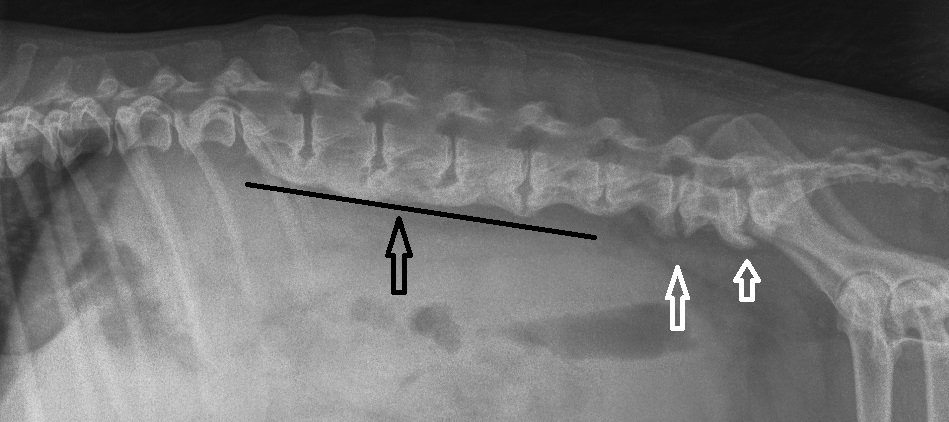

Mercredi 23 Janvier 2019 Animaux de compagnieChien griffon vendéen de 6 ans avec une DISH entre L1 et L6 très marquée (flèche noire) et une spondylose déformante entre L6-L7 et L7-S1 (flèche blanche). Le chien est asymptomatique. La différenciation DISH et SD est difficile.